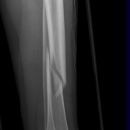

distaler Unterschenkelschaft

Spiralfraktur Tibia